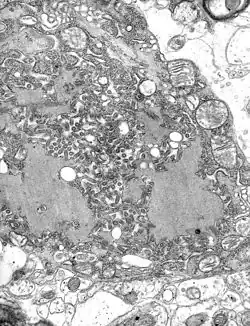

TEM micrograph with numerous rabies virions (small, dark grey, rodlike particles) and Negri bodies (the larger pathognomonic cellular inclusions of rabies infection)

The rabies virus is the type species of the Lyssavirus genus, in the family Rhabdoviridae, order Mononegavirales. Lyssavirions have helical symmetry, with a length of about 180 nm and a cross-section of about 75 nm.[34] These virions are enveloped and have a single-stranded RNA genome with negative sense. The genetic information is packed as a ribonucleoprotein complex in which RNA is tightly bound by the viral nucleoprotein. The RNA genome of the virus encodes five genes whose order is highly conserved: nucleoprotein (N), phosphoprotein (P), matrix protein (M), glycoprotein (G), and the viral RNA polymerase (L).[35]